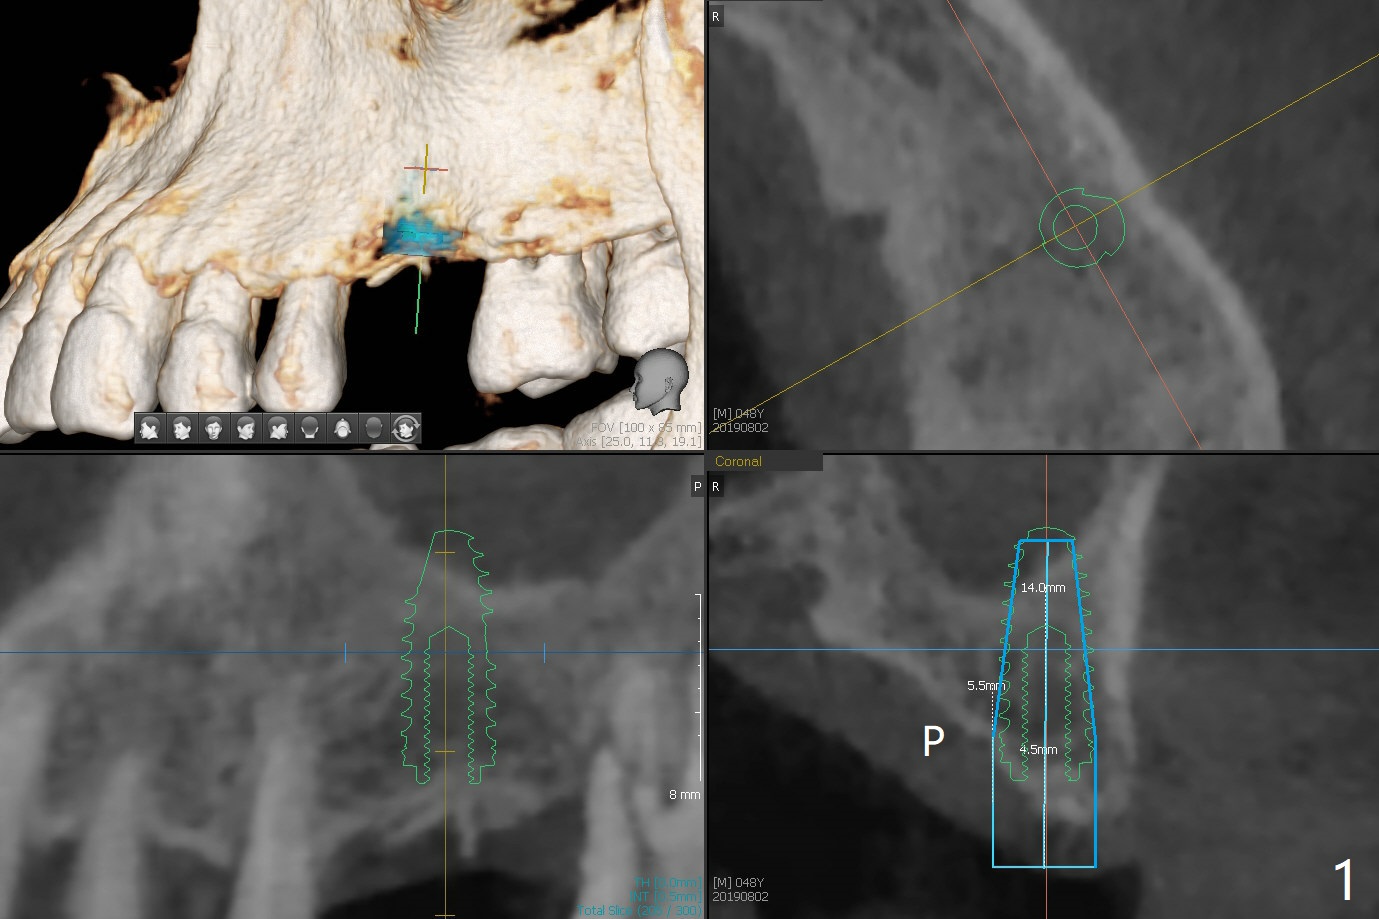

Immediately preop reanalysis of CT shows that there may be palatal thread exposure at #14 when a 4.5x14 mm tissue-level implant is placed equigingival (Fig.1,2). After sinus lift with IS 4x10 mm dummy implant with guide, the tissue-level tap and implant placed free hand look deep (Fig.3,3'). CT reveals possible 3 palatal threads exposed (Fig.4,5 arrowheads), which is associated with change in trajectory due to the palatal shift of the apex of the implant (arrow), as compared to the design of the bone-level implant (Fig.6). When there is a slope in the ridge and/or sinus floor, do not shift implants and use the guide for implant placement. If switching is necessary, use a final drill without underprep (Fig.7 red) through the sinus floor after sinus lift to avoid apical implant deviation. To fix the palatal thread exposure, palatal flap is raised. In fact the implant has to be removed for the incision. When the implant is re-placed deeper by ~ 1mm, there is a thread exposed. Bone graft is placed with collagen membrane. As a 4.5x3 mm abutment is placed, the implant is found to be unstable. Periodontal dressing is applied. In fact the implant exfoliates with the abutment 4.5 months postop (Fig.8). Bone graft seems to be necessary (sticky bone). Tissue level implant should be avoided for patient with poor oral hygiene. Return to Upper Molar Immediate Implant, Trajectory II 3 Xin Wei, DDS, PhD, MS 1st edition 08/30/2019, last revision 05/18/2020